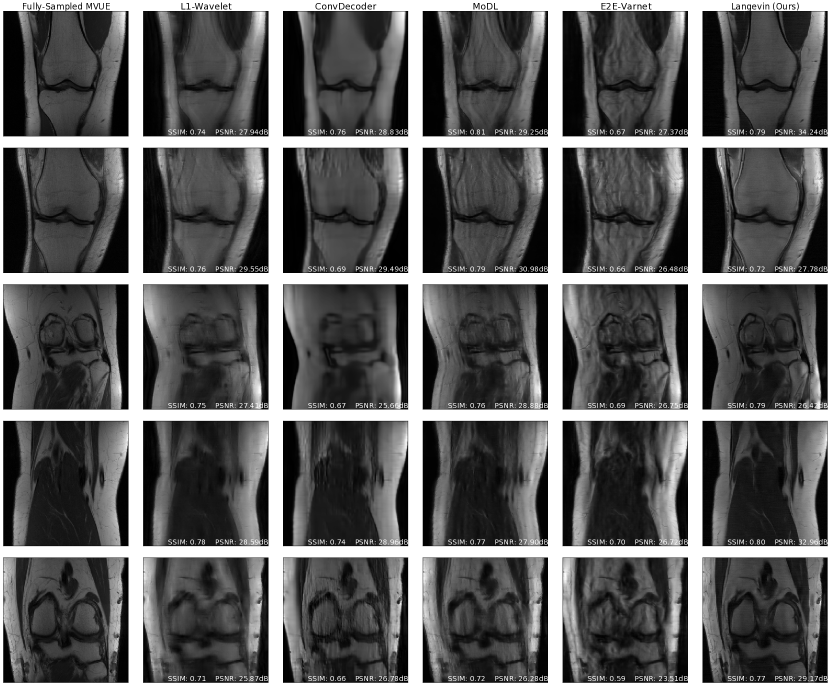

Refer to caption

Figure 1: Comparison of reconstruction methods for in-distribution, sampling-shift, and anatomy-shift images. All methods and hyperparameters were optimized on T2-weighted brain scans with a vertical sampling mask, and tested at higher accelerations, horizontal masks, and on knee & abdomen scans. Our reconstructions are competitive with state-of-the-art methods, and introduce fewer artifacts out of distribution. All measurements are multicoil k-space from the NYU fastMRI dataset and the supervised baselines are trained from scratch on MVUE targets for a fair comparison.

Our main results are succinctly summarized in Figure 1: we achieve equivalent reconstruction performance using a reduced training set when evaluated in-distribution and are robust when evaluated out-of-distribution.

Figure 1 (top three rows) shows qualitative results and Figures 2a & 5a respectively show PSNR & SSIM values, for the case where there is no mismatch between the training and inference sampling patterns. As the baselines were trained to maximize SSIM at R=3& 6𝑅36R=3\;\&\;6, we see that they achieve better SSIM scores than us at these accelerations, although there is clear aliasing in the baselines at R=6𝑅6R=6. We achieve better PSNR values at these accelerations, which supports the claim that our method does not overfit to a particular metric (Theorem 3.4). This also highlights the importance of qualitative evaluations in medical image reconstruction and the limitations of existing image quality metrics [65]. From the third row of Figure 1, and Figures 2a & 5a, we notice that our method surpasses baselines at higher accelerations.

Figure 1 (fourth row) shows qualitative reconstructions when the measurements are obtained from an equispaced, horizontal sampling mask, with an acceleration factor R=3𝑅3R=3. It can be observed that the reconstructions output by E2E-VarNet show aliasing artifacts. Based on the statistical results in Figure 2b & 5b, our method retains its performance.

Finally, Figures 2d & 5d show PSNR and SSIM scores obtained on fastMRI knee reconstructions, while Figure 1 (bottom row) shows the accompanying qualitative plots. This anatomy is challenging especially because of the poor signal-to-noise ratio conditions, which can be seen even in the ground-truth image. It can be noticed that this is the most severe shift for all methods, but our approach still shows the best performance at R=2,4𝑅24R={2,4} and a significantly lower variance. Appendix D shows more examples of knee reconstructions with and without fat suppression, and Figure 20 shows metrics on fat suppressed knees.